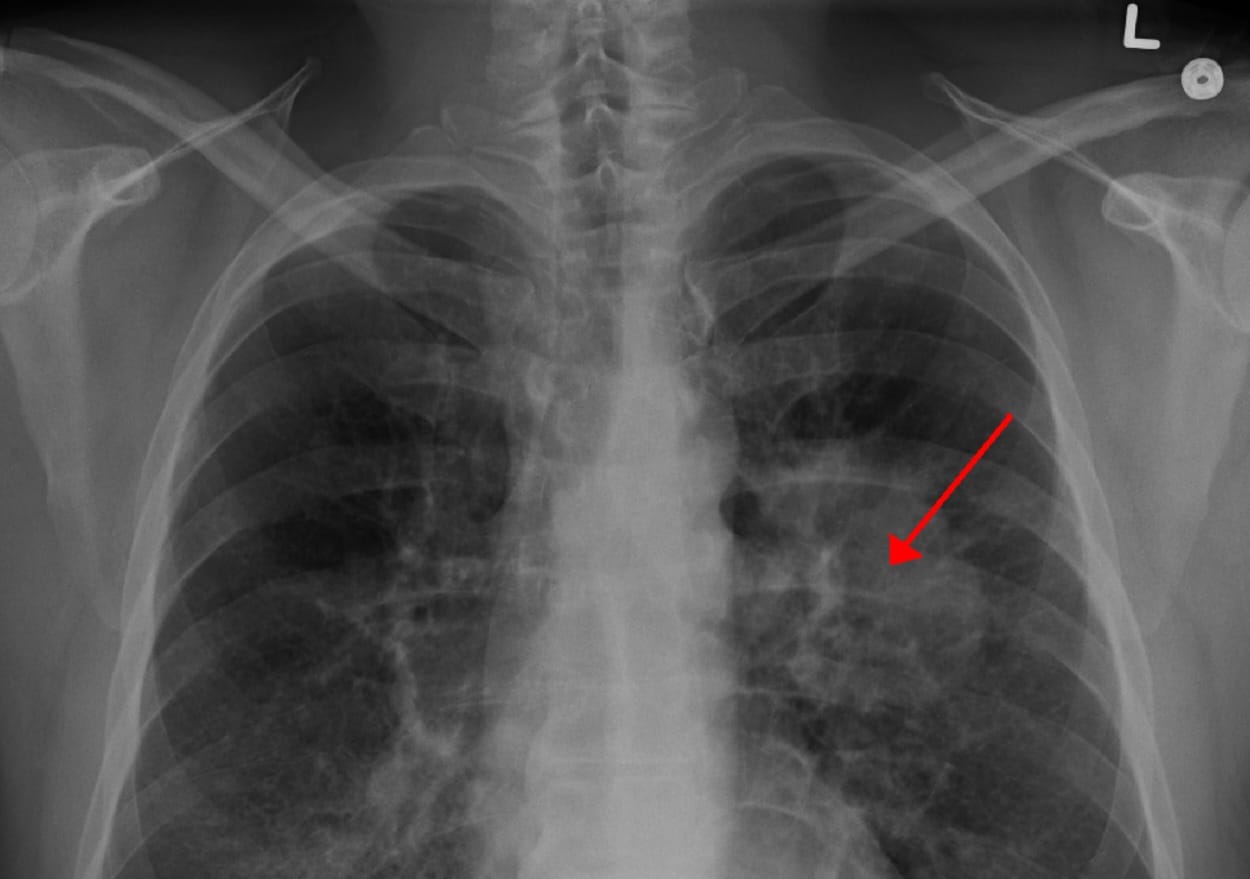

Ключевая особенность метода — использование красного и ближнего инфракрасного света с длиной волны около 800 нанометров. Это так называемое «окно прозрачности» биотканей: для такого излучения человеческое тело «прозрачно», как стекло. Свет беспрепятственно проникает сквозь кожу и мышцы, но поглощается наночастицами, накопленными в опухоли, вызывая их нагрев.

Помимо нагрева, крупные наночастицы способны закупоривать мелкие кровеносные сосуды, питающие новообразование. Доставленные непосредственно в опухоль, они под воздействием света запускают механизм ишемии, попросту перекрывая раковым клеткам доступ к кислороду и питательным веществам.